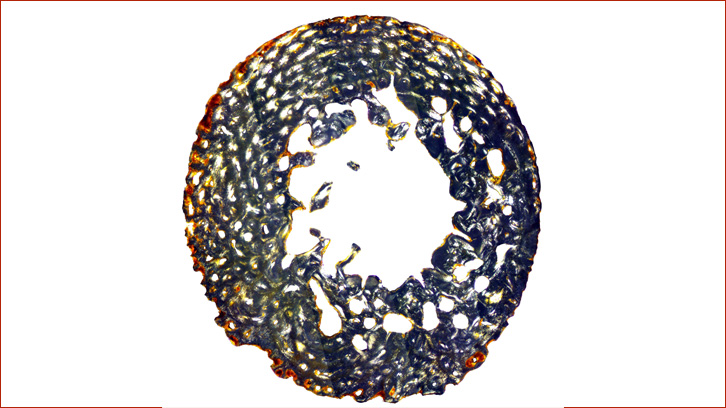

Els resultats són reveladors: els ossos dels individus preterme i dels nounats presenten una mineralització molt elevada, entre un 60 % i un 80 % de la secció transversal. Aquest patró reflecteix el procés normal de mineralització de l’esquelet abans del naixement. En concret, aquells individus que es troben en etapa de desenvolupament a terme i fins al primer mes de vida són els que presenten els valors més alts.

Després del primer mes, quan el nadó ja depèn dels seus propis processos metabòlics, aquesta mineralització disminueix i deixa una empremta visible al microscopi. Això permet, per primera vegada en l’estudi de la microestructura òssia, determinar si un individu ha arribat al període a terme i diferenciar-lo del període postnatal, una qüestió especialment complexa en bioarqueologia.